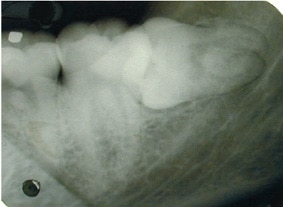

Tandlægen tager et røntgenbillede af visdomstanden for at se, hvordan tanden og roden ligger i kæben. Uanset om tanden skal trækkes eller opereres ud, bliver man lokalbedøvet. Derfor er det relativt smertefrit at få fjernet visdomstanden. Da man er ved fuld bevidsthed, kan man til gengæld både høre og fornemme, at der bliver arbejdet i ens mund. Man skal ikke være fastende før operationen.

Hos nogle er der en lille risiko for beskadigelse af følenerven, som kan ligge tæt på visdomstandens rod. Det er blandt andet derfor vigtigt, at der tages et godt røntgenbillede inden fjernelse af visdomstanden. Herved kan tandlægen bedømme, hvor tæt følenerven og visdoms tandens rod ligger. Hvis følenerven ligger tæt på roden, kan nerven blive beskadiget under operationen. Det kan resultere i følelsesløshed, snurren eller en sovende fornemmelse i en del af underlæben. Heldigvis er de fleste af sådanne føleforstyrrelser forbigående. I enkelte tilfælde kan de dog være vedvarende, hvilket kan være meget generende.

Billeder: Søren Hillerup​